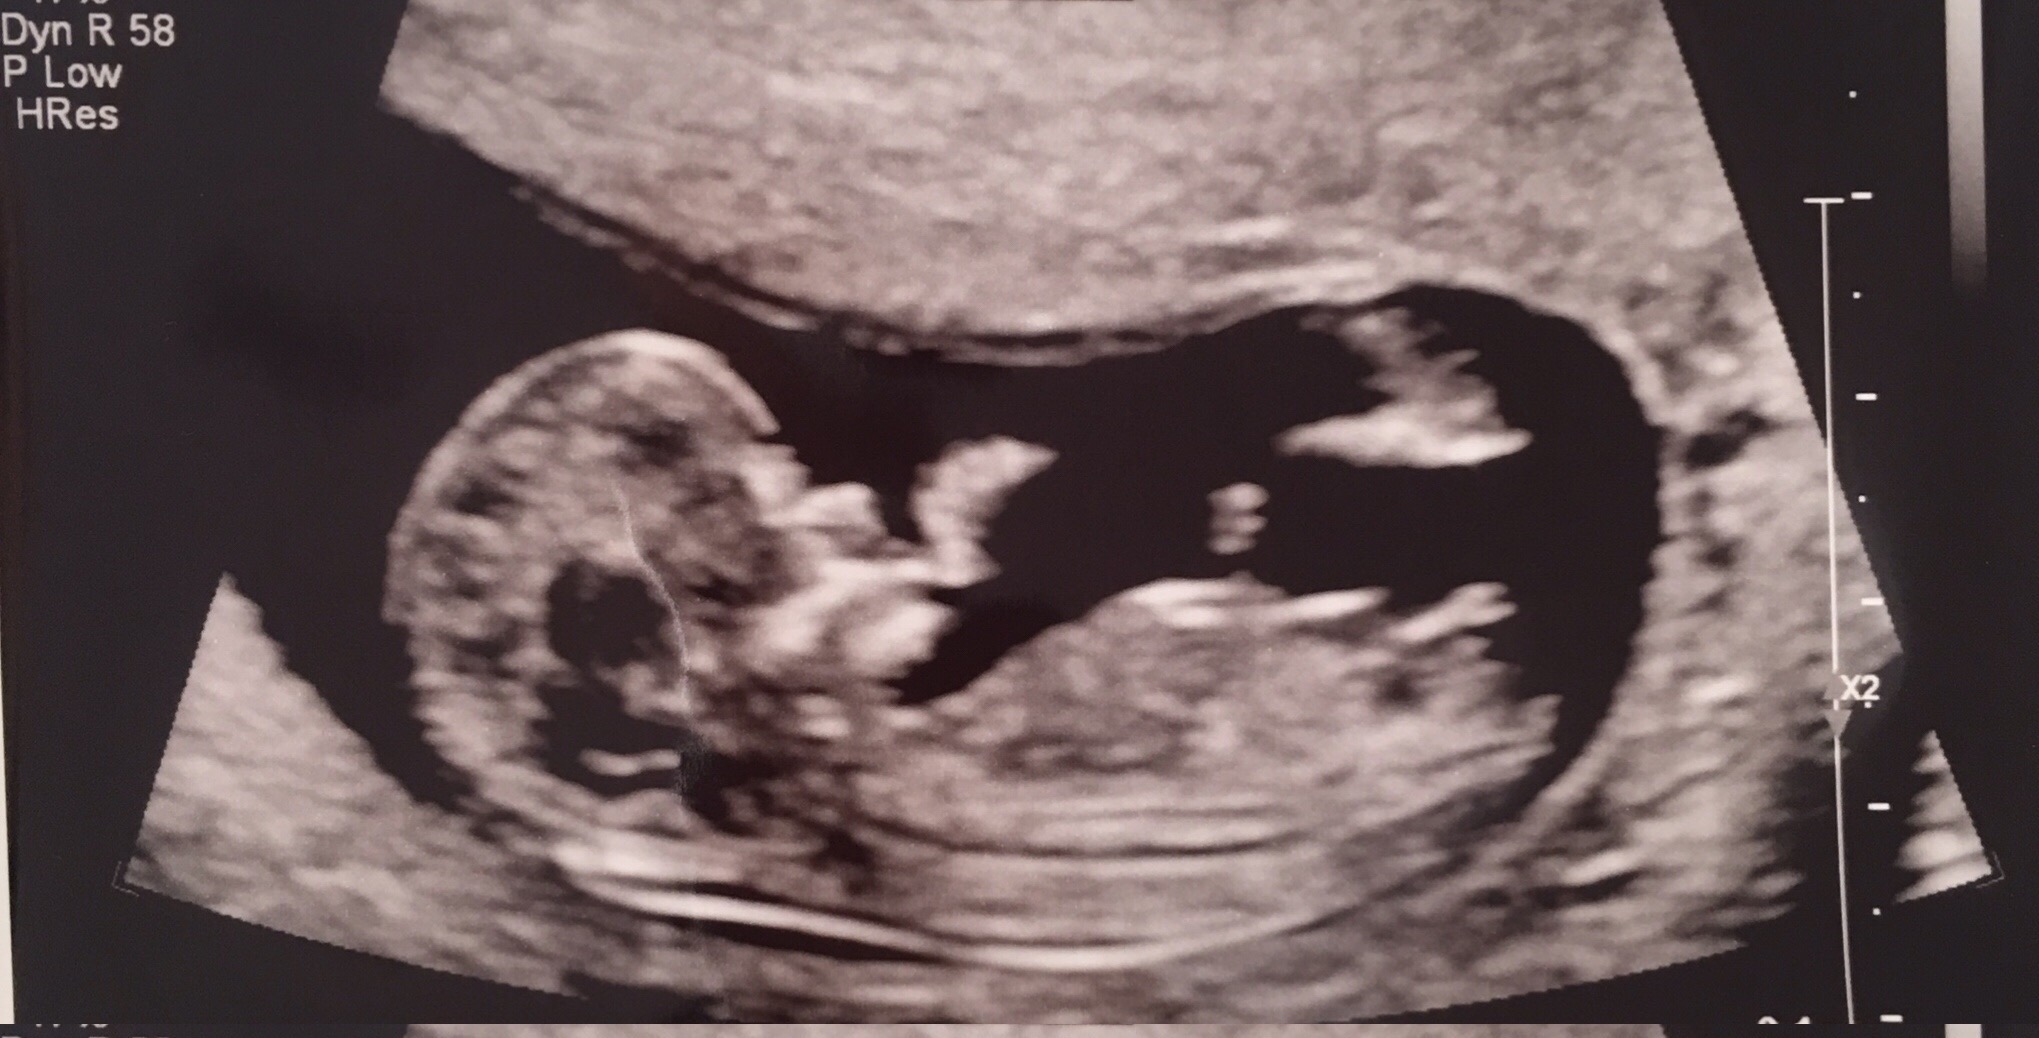

Patiently awaiting until I can find out baby's gender but in the meantime I'm obsessing over my scan!

Interested in hearing opinions based on nub...thank you!!Attachment 31527

Girl (I think!) What's the gestation?

12w 1d

Hmm that is early... There is something about this that looks like it's on the rise, but for the sake of guessing I'll stick with girl.

Normally 13 weeks is a better gestation for nub guesses. Yes don't buy anything yet! But I'd be hopeful for pink xx